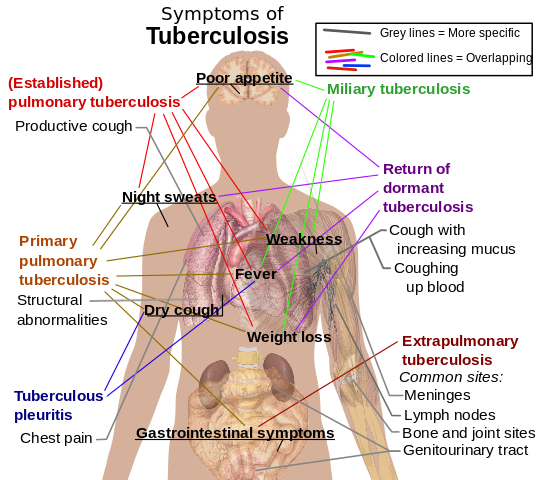

File:Tuberculosis symptoms.svg

| DescriptionTuberculosis symptoms.svg |

English: Main symptoms of different variants and stages of tuberculosis (See Wikipedia:Tuberculosis), with many symptoms overlapping with other variants, while others are more (but not entirely) specific for certain variants. Multiple variants may be present simultaneously.